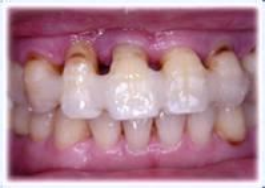

牙周炎的临床表现

牙龈红肿出血

2.牙齿松动脱落,溢脓